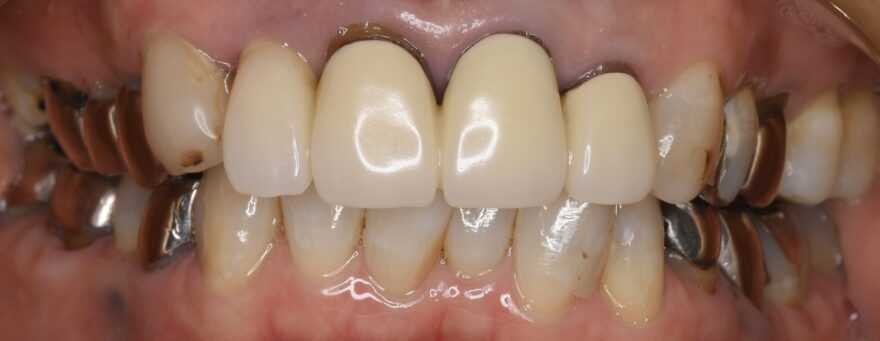

治療後の口腔内写真

*なお銀歯を含む全体的な治療も行なっています。